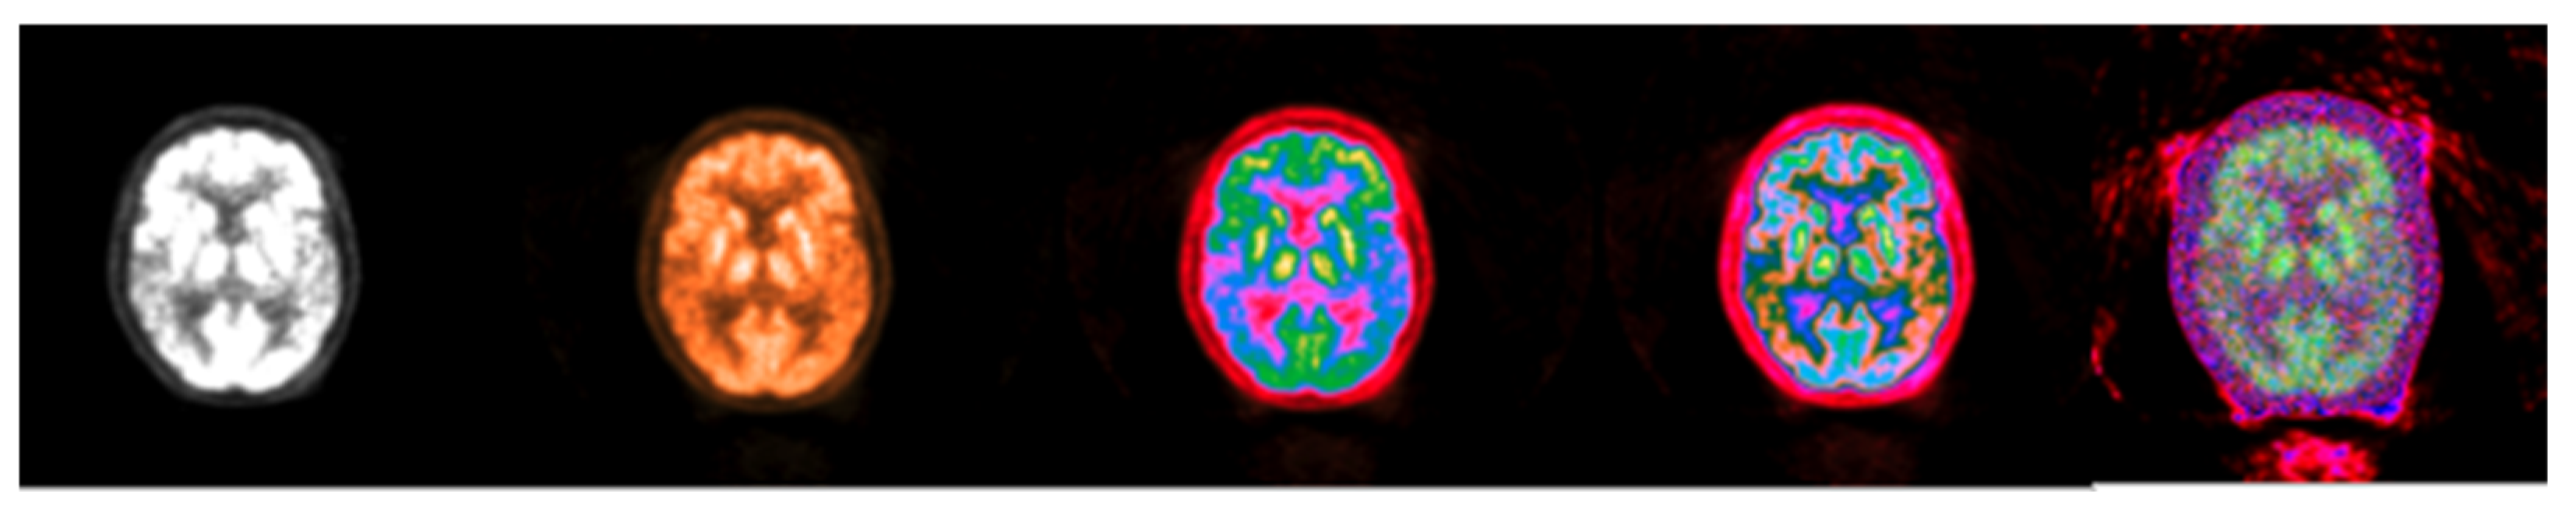

Figure 10.

Colormap Folding of PET image corresponding to CT slice in Figure 9 using 1, 2, 3, and 25 folds from Black to White (from (left) to (right)).

The results in Figure 9 suggest that the Colormap Folding of a CT image may not offer additional value to the original windowed grayscale CT (left). There is value, however, in applying Colormap Folding to PET. “Hidden” information in the standard grayscale version of the images (Figure 10 left) becomes visible and ROIs with different metabolic behavior may be identified and quantified using SUVs. From left to right, the second image already shows better visible information than the classic presentation. The third image starts to separate the tissues into color regions and the fourth image produces more detailed separations. Folding the PET image a higher number of times gives a higher resolution and, despite the noise, is still useful to the human observer.